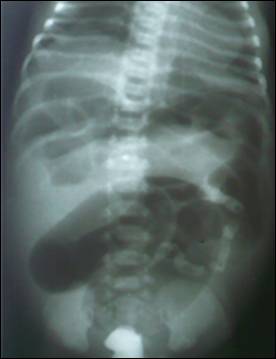

Figure 1: X-ray abdomen erect with gastrografin enema, showing small caliber of colon and filling defects.